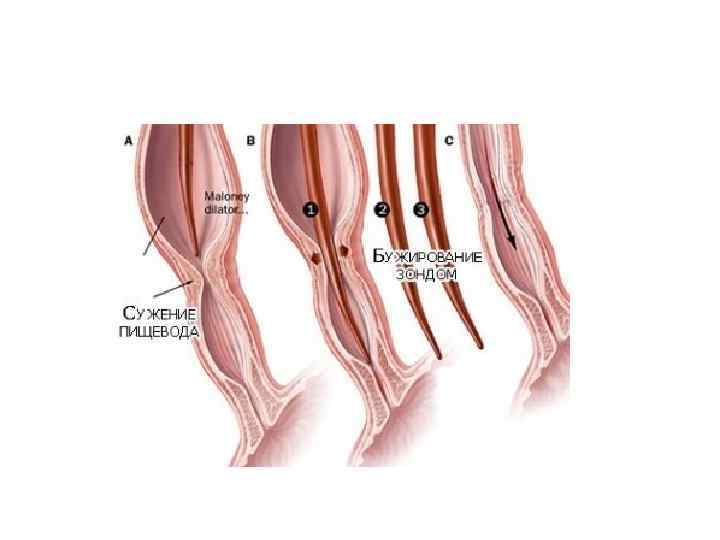

Бужирование пищевода • Рубцовый стеноз пищевода возникает через 1 -2 месяца. Если проводилось раннее бужирование, то образование стеноза происходит только у 4, 2 % больных, без профилактического бужирования – почти в 50 %. • Раннее бужирование начинают спустя 5— 10 дней (до 14 -го дня) после ожога. • Введенный в сужение буж оставляют в пищеводе на 15— 20 мин, а при тенденции к сужению — до 1 ч. На следующий день вводят на короткое время буж того же диаметра, а вслед за ним буж следующего номера, оставляя его в пищеводе на положенное время. При возникновении болезненной реакции, признаков недомогания, повышения температуры тела бужирование откладывают на несколько дней. • Ранее бужирование проводят ежедневно или через день в течение месяца даже при отсутствии признаков сужения пищевода, а затем в течение 2 мес по 1— 2 раза в неделю

Бужирование пищевода • Рубцовый стеноз пищевода возникает через 1 -2 месяца. Если проводилось раннее бужирование, то образование стеноза происходит только у 4, 2 % больных, без профилактического бужирования – почти в 50 %. • Раннее бужирование начинают спустя 5— 10 дней (до 14 -го дня) после ожога. • Введенный в сужение буж оставляют в пищеводе на 15— 20 мин, а при тенденции к сужению — до 1 ч. На следующий день вводят на короткое время буж того же диаметра, а вслед за ним буж следующего номера, оставляя его в пищеводе на положенное время. При возникновении болезненной реакции, признаков недомогания, повышения температуры тела бужирование откладывают на несколько дней. • Ранее бужирование проводят ежедневно или через день в течение месяца даже при отсутствии признаков сужения пищевода, а затем в течение 2 мес по 1— 2 раза в неделю

• Раннее бужирование у детей преследует цель предупреждения развития сужение просвета пищевода в фазе репаративных процессов рубцевания его пораженной стенки. По данным автора, начатое в первые 3— 8 дней после ожога бужирование не опасно для пострадавшего, так морфологически изменения в этот период распространяются только на слизистый и подслизистый слоя, и поэтому опасность перфорации минимальна. Показаниями для раннего бужирования служат нормальная температура тела в течение 2 -3 дней и исчезновение острых явлений общей интоксикации. Позже 15 -го дня с момента ожога бужирование становится опасным и для ребенка, так и для взрослого, так наступает фаза рубцевания пищевода, он становится ригидным и мало податливым, а стена не приобрела еще достаточной прочности.

• Раннее бужирование у детей преследует цель предупреждения развития сужение просвета пищевода в фазе репаративных процессов рубцевания его пораженной стенки. По данным автора, начатое в первые 3— 8 дней после ожога бужирование не опасно для пострадавшего, так морфологически изменения в этот период распространяются только на слизистый и подслизистый слоя, и поэтому опасность перфорации минимальна. Показаниями для раннего бужирования служат нормальная температура тела в течение 2 -3 дней и исчезновение острых явлений общей интоксикации. Позже 15 -го дня с момента ожога бужирование становится опасным и для ребенка, так и для взрослого, так наступает фаза рубцевания пищевода, он становится ригидным и мало податливым, а стена не приобрела еще достаточной прочности.

• Лечебное бужирование следует применять не ранее 7 нед после ожога, т. к. при бужировании пищевода в сроки от 2 до 6 нед после ожога происходит разрушение бужом грануляций и свежей соединительной ткани. В этот период наиболее часто отмечают перфорации пищевода.

• Лечебное бужирование следует применять не ранее 7 нед после ожога, т. к. при бужировании пищевода в сроки от 2 до 6 нед после ожога происходит разрушение бужом грануляций и свежей соединительной ткани. В этот период наиболее часто отмечают перфорации пищевода.

• • При пальпаторном введении бужа больной сидит со слегка наклоненной вперед головой. Врач левым указательным пальцем отдавливает корень языка вперед и вниз, а правой рукой, строго придерживаясь средней линии, вводит буж в нижний отдел глотки, а затем в пищевод (рис. 289). При этом в какой-то момент врач ощущает препятствие, соответствующее верхней границе сужения. На буже делается отметка о расстоянии до начала сужения. Если буж не входит в стриктуру, последовательно вводятся бужи меньших размеров до тех пор, пока один из них не пройдет в сужение. А - правильное положение головы; Б - неправильное положение головы.

• • При пальпаторном введении бужа больной сидит со слегка наклоненной вперед головой. Врач левым указательным пальцем отдавливает корень языка вперед и вниз, а правой рукой, строго придерживаясь средней линии, вводит буж в нижний отдел глотки, а затем в пищевод (рис. 289). При этом в какой-то момент врач ощущает препятствие, соответствующее верхней границе сужения. На буже делается отметка о расстоянии до начала сужения. Если буж не входит в стриктуру, последовательно вводятся бужи меньших размеров до тех пор, пока один из них не пройдет в сужение. А - правильное положение головы; Б - неправильное положение головы.

• Бужирование через рот (вслепую). При небольшом сужении пищевода. При сформировавшихся рубцовых сужениях следует ежедневно или каждые 2 дня вводить буж возрастающего размера (до 3840 го). Затем бужируют 2 раза в неделю и 1 раз в месяц в течение года.

• Бужирование через рот (вслепую). При небольшом сужении пищевода. При сформировавшихся рубцовых сужениях следует ежедневно или каждые 2 дня вводить буж возрастающего размера (до 3840 го). Затем бужируют 2 раза в неделю и 1 раз в месяц в течение года.

• Бужирование под контролем эзофагоскопа. • Бужирование по металической струне-проводнику.

• Бужирование под контролем эзофагоскопа. • Бужирование по металической струне-проводнику.